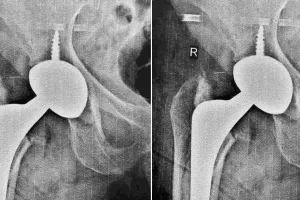

राजस्थान में गर्भवती महिलाओं को खून की कमी का इलाज आयरन का इंजेक्शन लगाकर होगा। राजस्थान मेडिकल सर्विस कॉरपोरेशन से इसकी खरीद हो चुकी है। अब इसे अस्पतालों में सप्लाई किया जा रहा है। इंजेक्शन अत्याधिक गंभीर खून की कमी वाली गर्भवती महिलाओं को दिया जाएगा, ताकि प्रसव से पूर्व शरीर में खून की कमी को तेजी से दूर किया जा सके। 40-50 की उम्र में घुटने बदलने की जरूरत नहीं, एच टी ओ तकनीक बचा सकती है प्राकृतिक घुटना

40 से 50 वर्ष की उम्र में ही लोगों के घुटनों में दर्द शुरू हो जाता है और पैर अंदर की तरफ मुड़ने लगते। मरीज को लगता है कि अब नी रिप्लेसमेंट ही एकमात्र रास्ता बचा है। लेकिन यह धारणा गलत। ऑर्थोपेडिक सर्जन एवं जोड़ प्रत्यारोपण विशेषज्ञ डॉ. आशीष राणा गोयल बताते हैं कि कम उम्र के और सक्रिय मरीजों के लिए रिप्लेसमेंट के बजाय हाई टिबियल ऑस्टियोटॉमी एक बेहतर विकल्प है, जिससे नेचुरल घुटने को 10-15 साल तक बचाया जा सकता। दैनिक नवज्योति के स्थापना दिवस पर रक्तदान शिविर : 31 रक्तवीरों ने किया रक्तदान, आरके अस्पताल में मरीजों को फल और बिस्किट किए वितरण